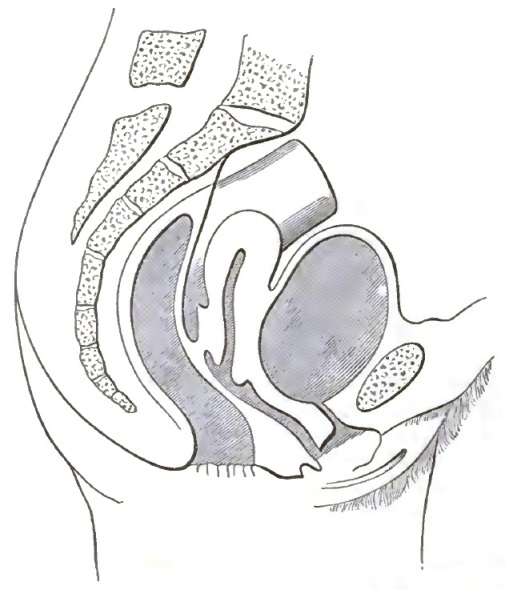

| 1. | THE CLASSICAL REPRESENTATION OF THE PELVIC ORGANS |

| 2. | THE CORRECT REPRESENTATION OF THE PELVIC ORGANS |